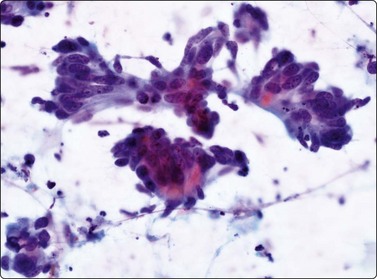

Fig. 10.27 Cholangiocarcinoma

(A) Disorganized clusters of irregular but not very pleomorphic tumor cells with pale cytoplasm and relatively small nuclei (MGG, HP); (B) Disorganized cluster of mildly pleomorphic epithelial cells with hyperchromatic nuclei and prominent nucleoli (MGG, HP); (C) Corresponding tissue section (H&E, IP).

Criteria for diagnosis (Fig. 10.27)172

Sheets, clusters and microglandular arrangement showing nuclear crowding and overlapping,

Decreased cell cohesion,

Small to medium cuboidal/columnar cells resembling bile duct epithelium,

Variable nuclear enlargement and pleomorphism,

Prominent nucleoli in the less well-differentiated tumors,

Delicate cytoplasm with fine vacuolization, positive for mucin,

Occasionally fragments of stroma.

Cholangiocarcinomas often have abundant, desmoplastic stroma and may prove difficult to sample by FNA, or CNB for that matter. Although cells from a well-differentiated cholangiocarcinoma may not appear too different from bile duct epithelium, hepatocytes are absent and the number and size of epithelial sheets are larger than are usually obtained from non-neoplastic liver tissue (Fig. 10.27A). The application of P53, bcl-2 and Ki-67 has been reported as useful in discriminating between them.173 Less well-differentiated carcinomas are indistinguishable from metastatic adenocarcinoma (Fig. 10.27B), particularly those of pancreatic origin. Unfortunately, they are both generally positive for CK7 and CK19 and negative for CK20.174 Distinction from HCC relies on adenocarcinoma showing positivity for mucin and diffuse cytoplasmic staining for CK7, CK19 and pCEA and HCC staining for alpha fetoprotein and HepPar-1 and others as described earlier in the section on HCC.